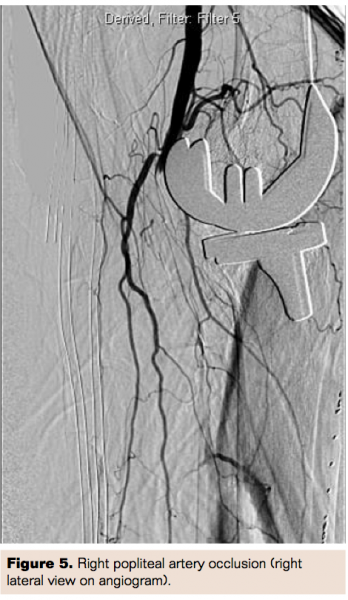

The patient was taken to the cardiac catheterization lab and initial diagnostic angiogram through the right radial approach showed right popliteal artery and right anterior tibial occlusion (Figure 5). The patient was scheduled the next day for endovascular intervention of the right popliteal artery.

nitial access was obtained in the right common femoral artery in an antegrade fashion using 6 French 30 cm long Ansel sheath. Heparin was used for anticoagulation. Initial attempts were made to cross the lesion using a 0.014˝ Command ES wire (Abbott Vascular) and Rubicon 0.018˝ crossing catheter (Boston Scientific). However, it was difficult to clearly define the proximal cap and course of the popliteal artery due to extensive collaterals as well as poor visualization due to the knee implant.